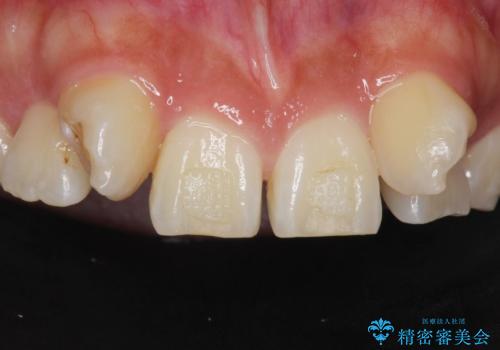

- 生まれつき上の側切歯と犬歯が逆に生えていることを主訴に来院された患者様です。

他院で矯正を行っていたそうですが、なかなか終わらないため途中で治療をやめてしまったとのことでした。

矯正以外の治療法で早く治したいとのご希望により、上顎両側犬歯を抜去しオールセラミックのブリッジによる補綴治療を行いました。